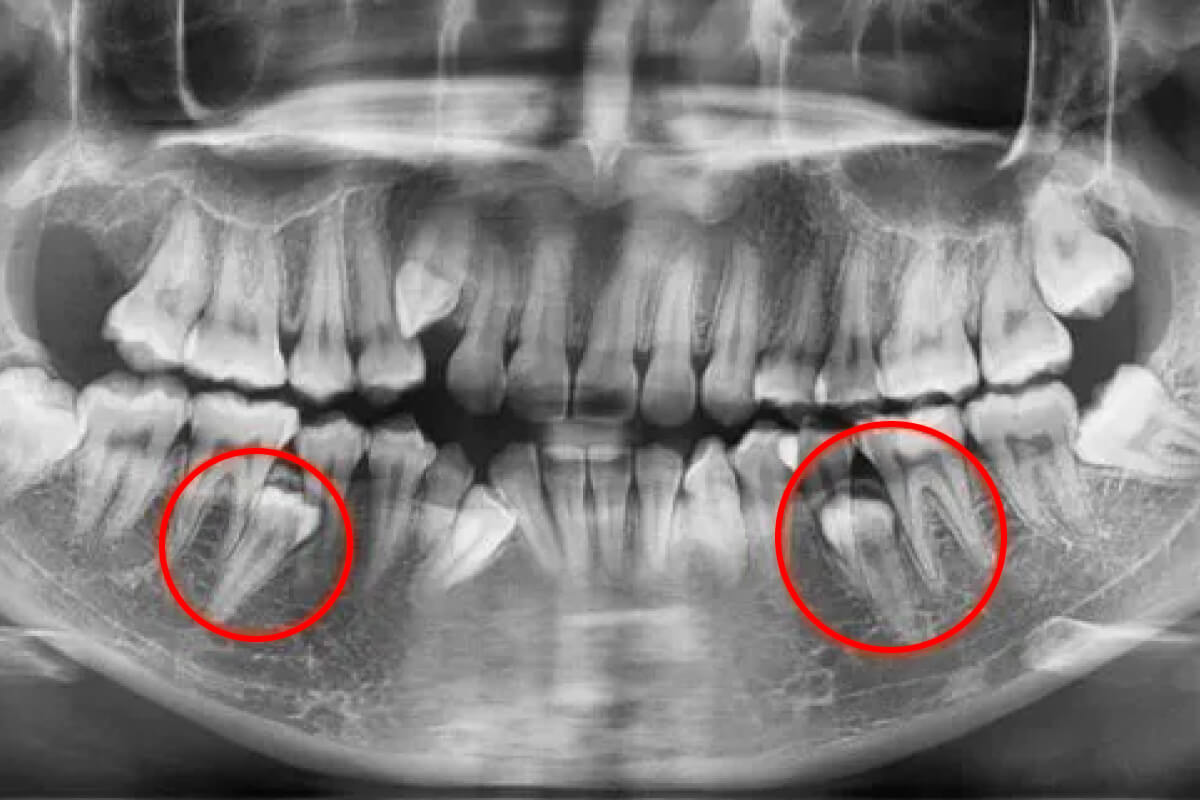

• Neprerezané zuby múdrosti (osmičky): Často zostávajú ukryté pod ďasnom alebo rastú nakrivo a tlačia na ostatné zuby. V takom prípade je extrakcia zuba múdrosti dôležitá.

Chirurgická extrakcia osmičiek | Dental Centrum NIVY